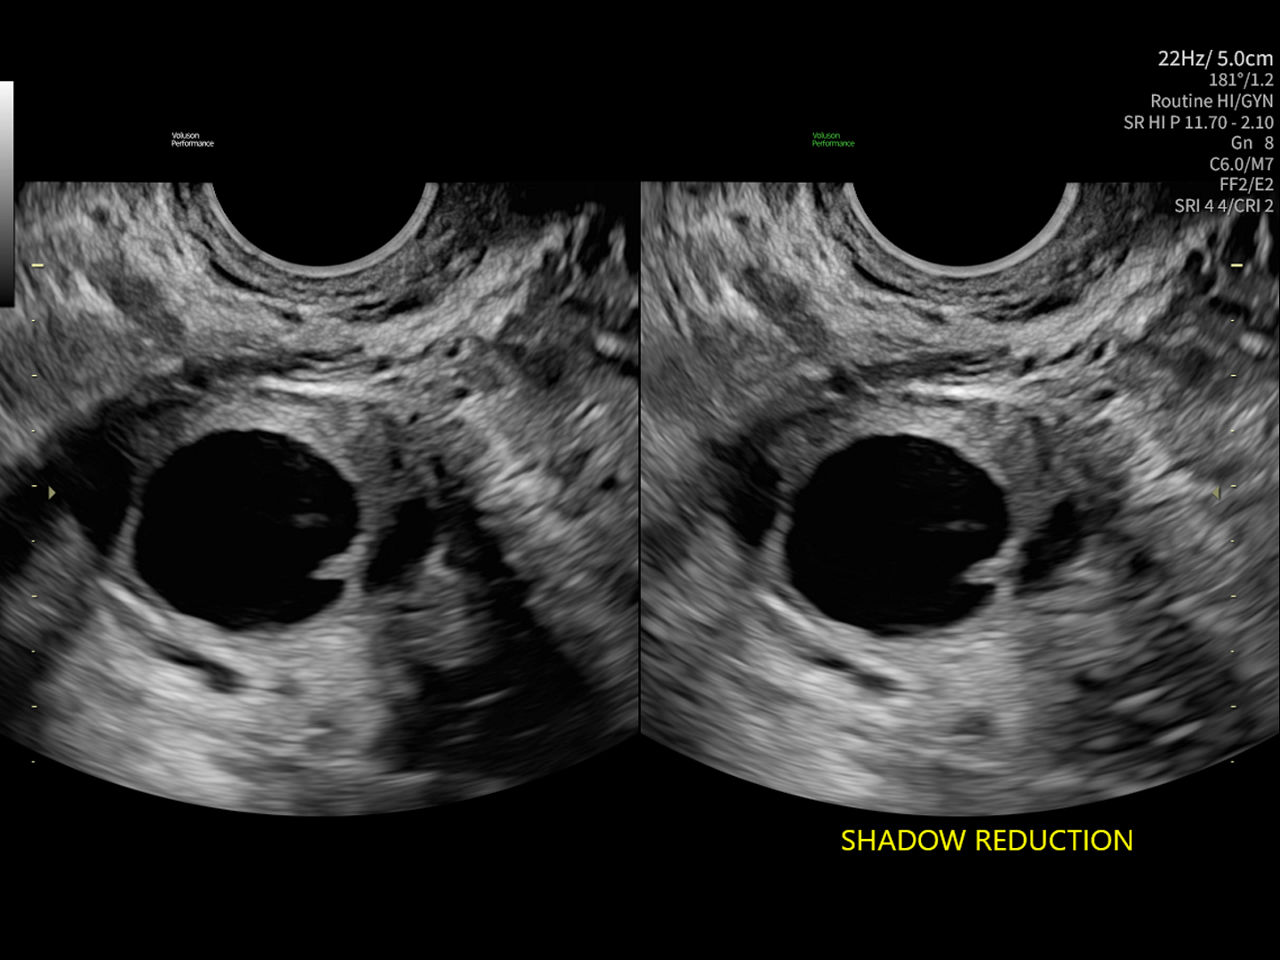

Shadow Reduction

Confident answers

Shadow Reduction decreases shadows on B-mode imaging that can obscure adjacent structures, helping restore tissue information and borders.